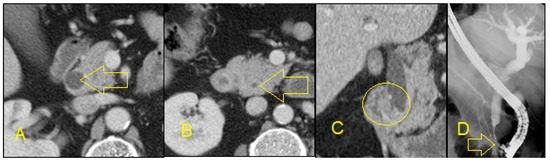

5. Non-Invasive Imaging Studies

- Feldman, M.K.; Coppa, C.P. Noninvasive imaging of the biliary tree for the interventional radiologist. Tech. Vasc. Interv. Radiol. 2015, 18, 184–196. [Google Scholar] [CrossRef]

- Baron, R.L.; Tublin, M.E.; Peterson, M.S. Imaging the spectrum of biliary tract disease. Radiol. Clin. 2002, 40, 1325–1354. [Google Scholar] [CrossRef]

- Singh, A.; Gelrud, A.; Agarwal, B. Biliary strictures: Diagnostic considerations and approach. Gastroenterol. Rep. 2015, 3, 22–31. [Google Scholar] [CrossRef] [PubMed]

- Rösch, T.; Meining, A.; Frühmorgen, S.; Zillinger, C.; Schusdziarra, V.; Hellerhoff, K.; Classen, M.; Helmberger, H. A prospective comparison of the diagnostic accuracy of ERCP, MRCP, CT, and EUS in biliary strictures. Gastrointest. Endosc. 2002, 55, 870–876. [Google Scholar] [CrossRef] [PubMed]